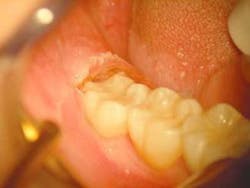

The restorative treatment was completed without incident using micro-air-abrasion techniques. The restoration was placed and cured with a Lasermed Argon Laser (Fig. 3). The healing phase was unremarkable.